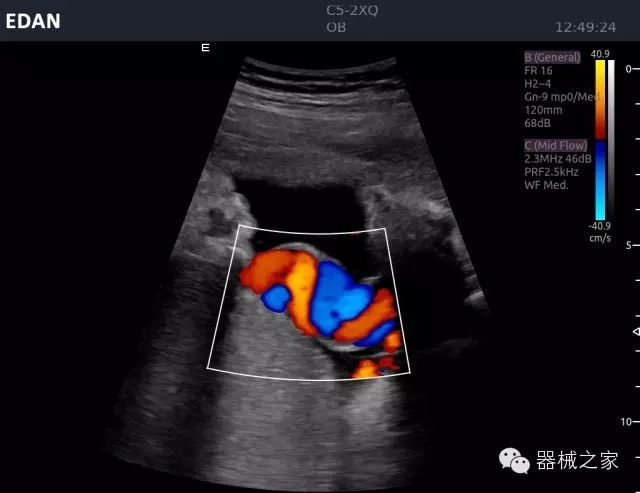

品牌:理邦儀器(EDAN)

公司簡介:

理邦立足健康產(chǎn)業(yè),以全球化的視野、持續(xù)的創(chuàng)新和卓越的服務(wù),成為國內(nèi)規(guī)模最大的醫(yī)療健康產(chǎn)品、解決方案和服務(wù)提供商之一。涵蓋病人監(jiān)護、心電產(chǎn)品、超聲影像、婦幼健康、體外診斷、智慧健康六大業(yè)務(wù)板塊。在中國,理邦輻射全國市場的服務(wù)網(wǎng)絡(luò)已為超過17000家醫(yī)療機構(gòu)提供了創(chuàng)新型、高品質(zhì)的產(chǎn)品和服務(wù)。在全球設(shè)立五大研發(fā)中心、14個子公司,產(chǎn)品遠銷150多個國家和地區(qū)。全球醫(yī)療專家信賴理邦突破性的醫(yī)療技術(shù)和出色的客戶服務(wù)。(理邦儀器SHE:300206)

官方網(wǎng)站:www.edan.com.cn

經(jīng)典產(chǎn)品:Acclarix AX8

臨床圖片賞析

睪丸低速血流

臍帶血流

頸動脈頻譜

產(chǎn)品特點

·新視界、高效能、新體驗;

·別具匠心的獨特設(shè)計、創(chuàng)新工作流、強大的功能組合以滿足POC圖像的需求;

·15英寸高分辨率顯示器;

·10.1英寸防指紋觸摸屏;

·獨一無二的觸控式軌跡球;

·超聲模塊的便攜式設(shè)計;

·128物理通道;

·UPS持續(xù)供電;

多項前沿圖像技術(shù)

·復(fù)合成像 波束合成 頻率復(fù)合 噪聲抑制等;

穿刺針增強技術(shù)

·顯著增強針體 清晰識別結(jié)構(gòu)、位置等比鄰關(guān)系;

多種成像模式

·梯形成像 寬景成像 3D成像 特征成像等;

CFDA注冊證編號

·粵械注準(zhǔn)20152230912